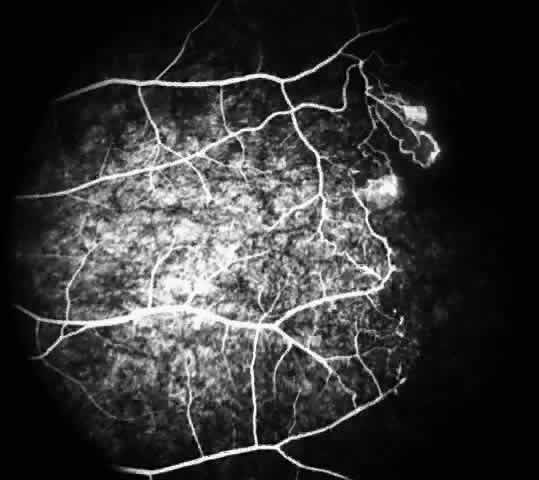

Fluorescein angiography remains the best method of identifying these peripheral retinal changes and documenting the presence of neovascularization.19

STAGE I: PERIPHERAL ARTERIOLAR OCCLUSIONS. This stage may be further subdivided into three grades: grade I, narrowing of the peripheral arterioles with tortuosity and abnormal looping of the peripheral venules; grade II, tortuosity, dilation, and microaneurysmal formation in the capillary network; and grade III, occlusion of the peripheral capillaries and arterioles.83

The occluded arterioles may be invisible or may have a “silver-wire” or chalk-white appearance, as first described by Goodman and colleagues39 (Fig. 21). Fluorescein angiography may demonstrate an abrupt complete occlusion at the interface between peripheral nonperfused and posterior perfused retina. Frequently, this occlusion will take place just distal to a branching vessel, giving the appearance of a freshly pruned rose bush. The nonperfused anterior peripheral retina will have a grayish brown appearance and on fluorescein angiography will appear blurred without clearly defined fundus markings.

Fig. 21. A. Photograph of the peripheral retinal vasculature shows sheathed vessels and absence of peripheral vascular perfusion. B. Fluorescein angiogram shows area of nonperfusion representing stage I sickle cell retinopathy. White arrow points to corresponding vascular bifurcation in A and B.

STAGE II: PERIPHERAL ARTERIOLAR-VENULAR ANASTOMOSES. Following occlusion of the terminal arterioles, anastomotic channels form to channel the blood from the occluded arteriole to the nearest venules. These anastomoses form at the interface between the perfused and nonperfused retina. Most likely, they are dilated preexisting capillaries rather than new vessels, since they do not leak on fluorescein angiography. The redirection of blood flow is probably due to hydrostatic forces (Figs. 22 and 23).

Fig. 22. A. Photograph of the peripheral retina, demonstrating capillary occlusions and exudate at the margin of perfused retina. B. Fluorescein angiogram of irregular capillary border, with capillary stumps extending into nonperfused retina and an arteriolar-venular anastomosis demonstrating stage II retinopathy.

Fig. 23. Fluorescein angiogram of continuous arteriolar-venular anastomosis demonstrating stage II retinopathy. (Note that this is the same eye demonstrating the qualitatively abnormal peripheral capillary border in Figure 25.)